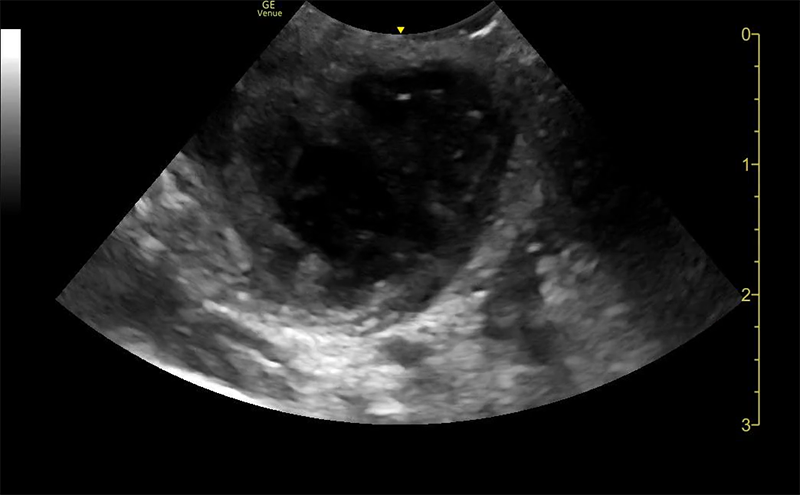

Pus Club

These champions have dominated a peritonsilar abscess!